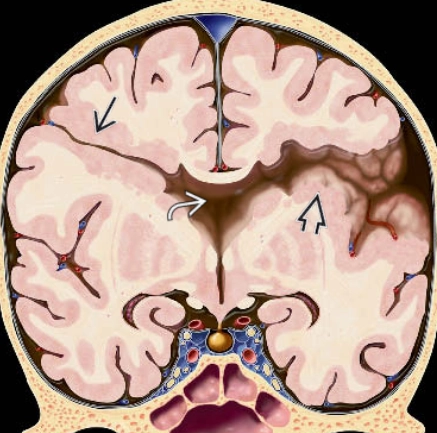

• Đa hồi não nhỏ (Polymicrogyria)

• Nhẵn não (Lissencephaly)- CT,MRI

• Nứt não (Schizencephaly)

• To một bên bán cầu não (Hemimegalencephaly - HMEG)